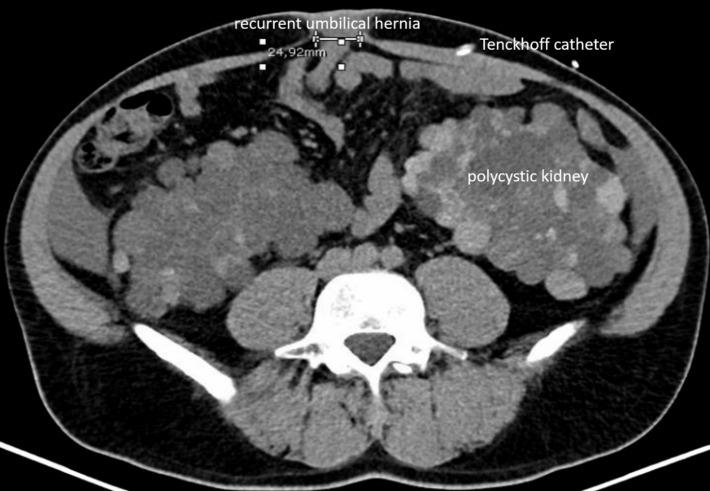

Abdominal wall hernias are frequent in patients with peritoneal dialysis. Guidelines recommend an open hernia repair with extraperitoneal mesh placement to avoid access to the abdominal cavity. We performed a lateral docking robotically assisted enhanced-view totally extraperitoneal repair (eTEP) of a recurrent umbilical hernia with diastasis recti in a patient with peritoneal dialysis due to polycystic kidney disease. After suturing of the midline a 20 x 28 cm mesh was placed in the retrorectus space, covering the whole area of preparation while also overlapping all trocar sites. A drainage was left in the retrorectus space until the first session of PD did not sample any form of leakage. Robotically assisted totally extraperitoneal hernia repair was feasible. The patient was able to continue peritoneal dialysis without intermittent hemodialysis. There was no leakage of the dialysate to the retrorectus space. Postoperative recovery was uneventful. 6 months after surgery the patient was free from pain and showed no signs of recurrence. Robotically assisted totally extraperitoneal hernia repair in patients with umbilical hernia and peritoneal dialysis could be a promising surgical technique to combine the advantages of minimally-invasive surgery with totally extraperitoneal mesh placement without access to the abdominal cavity.